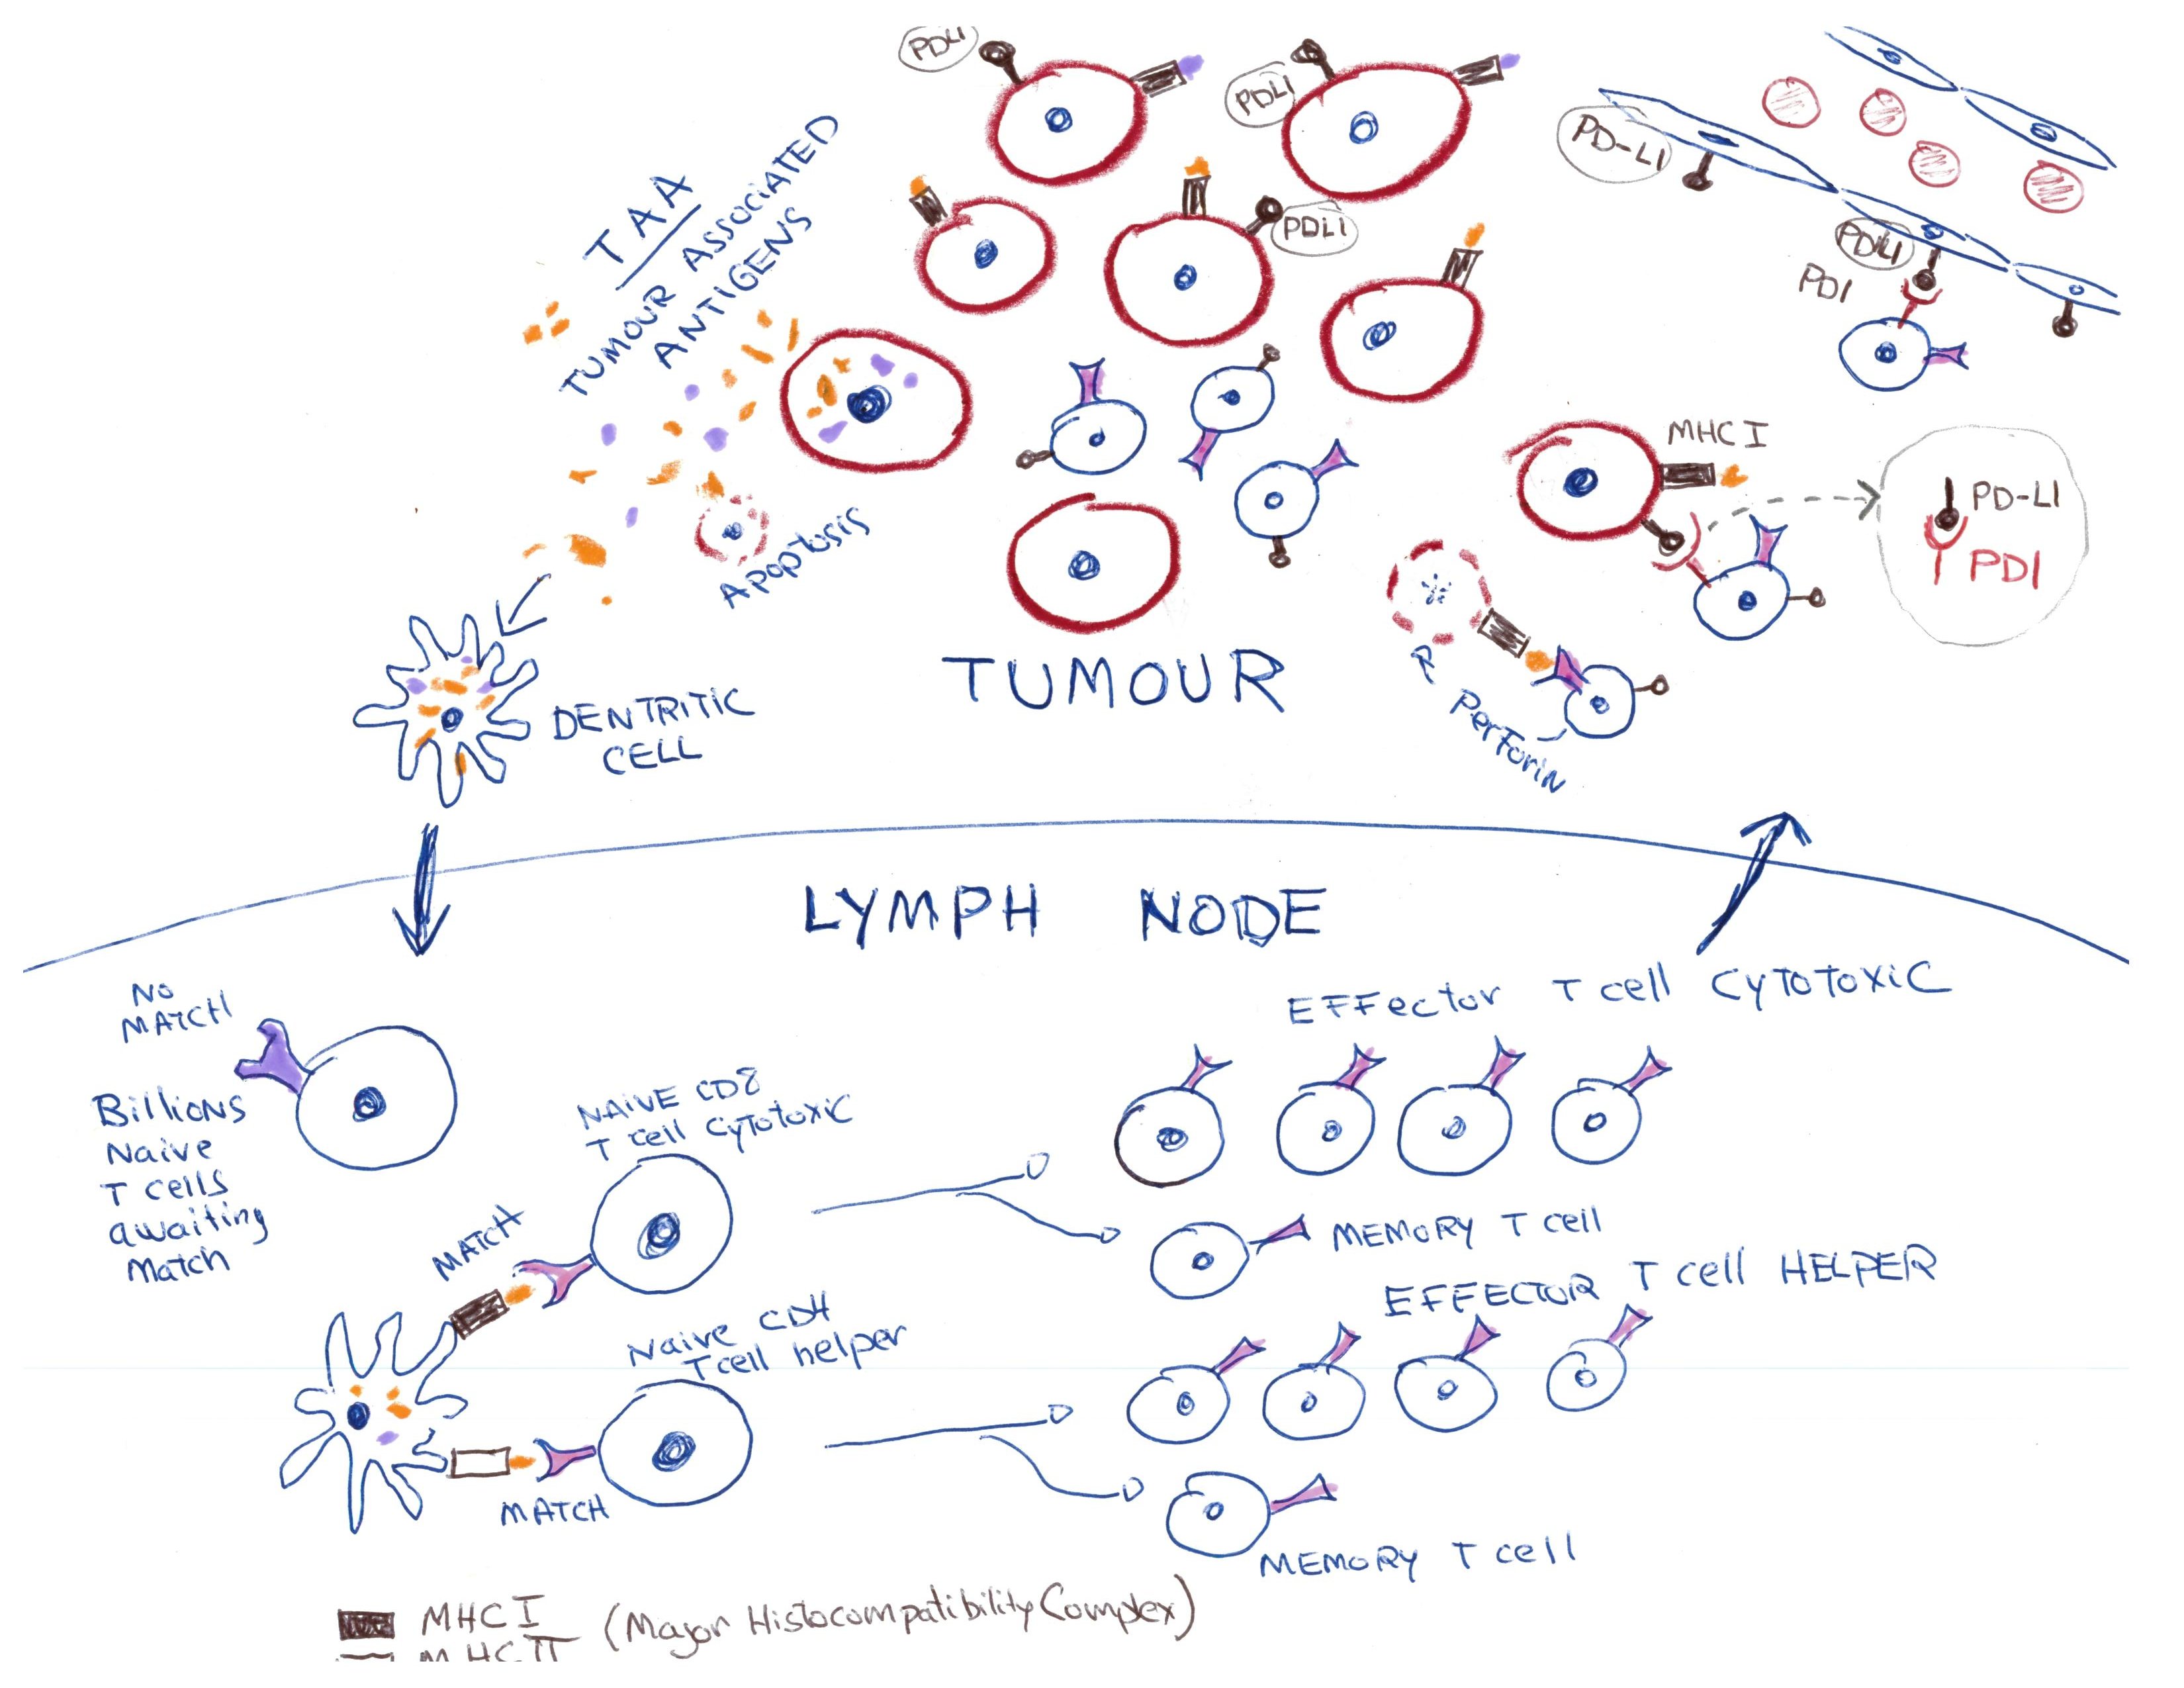

Adaptive cellular immunity triggered by "foreign" antigens (virus, cancer, etc.)